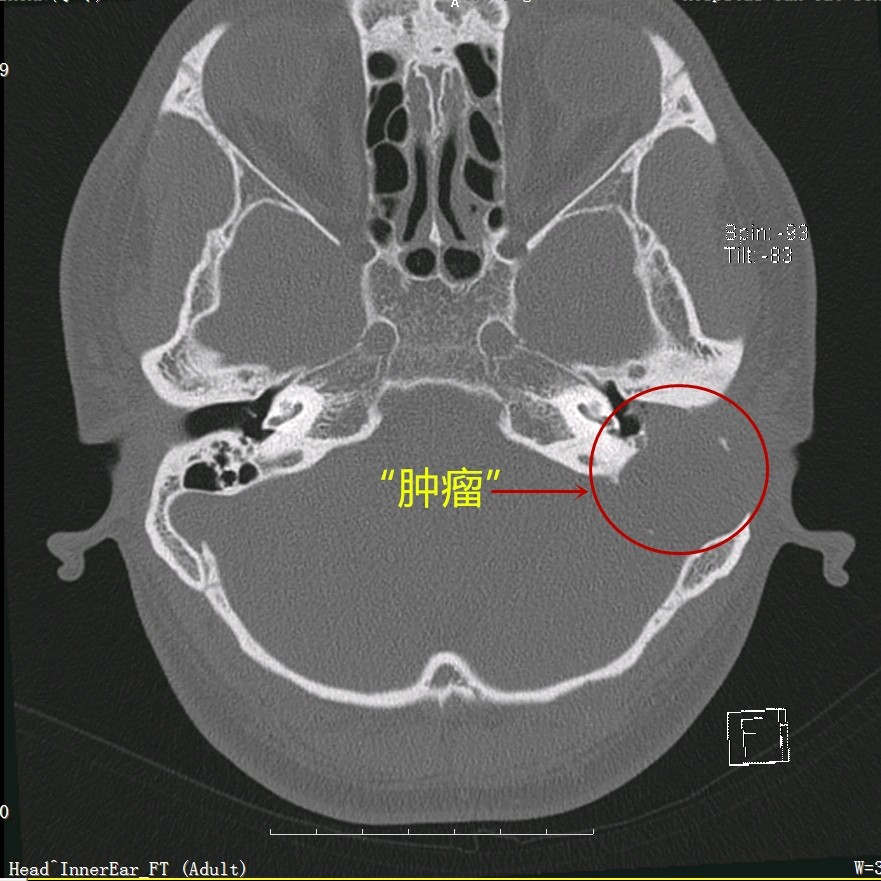

从李先生的CT片子可以见到其左侧中耳乳突巨大软组织影,并有周围骨质破坏,乙状窦前壁和天盖已不完整,部分颅脑组织都受到了挤压,提示“肿瘤”已经破坏周围骨质了,结合患者病史、体征及相关检查,考虑胆脂瘤型中耳炎可能,由于位置特殊,同时伴有骨质破坏、缺损,周围有重要的结构,如乙状窦、硬脑膜、颅脑、面神经等,如颅内留置了一颗“不定时炸弹”,疾病若进一步发展,李先生便有相关颅内、颅外并发症发生的风险,严重时甚至致命。

得知病情严重,李先生立刻入院治疗,在加强抗感染同时,完善颅脑MR、鼻内镜、耳内镜、听力学等检查,幸运地是,虽然“肿瘤”巨大,但颅脑MR示硬脑膜尚完整,且患者目前并没有面神经受损麻痹的面瘫症状,这些为手术创造了有利条件。